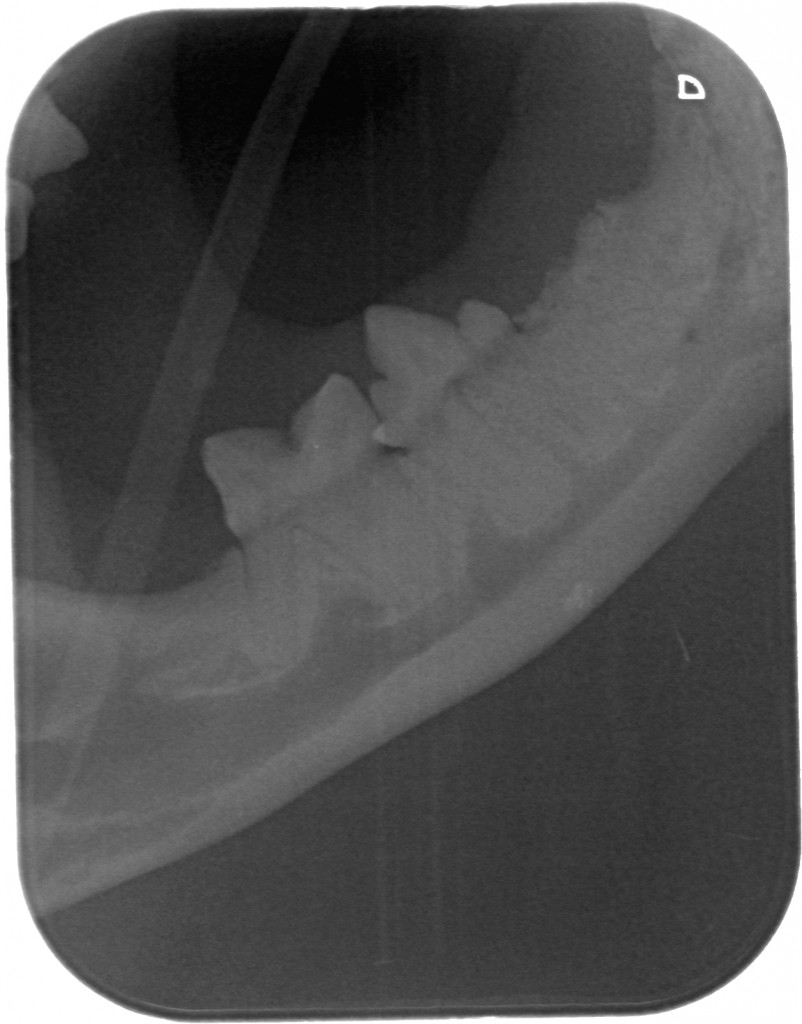

www.kattensliv.dk_Sygdomme hos katte fra P-T_Tænder_Mundproblemer_Shana-Mio_5

Fuld størrelse er

802 × 1024